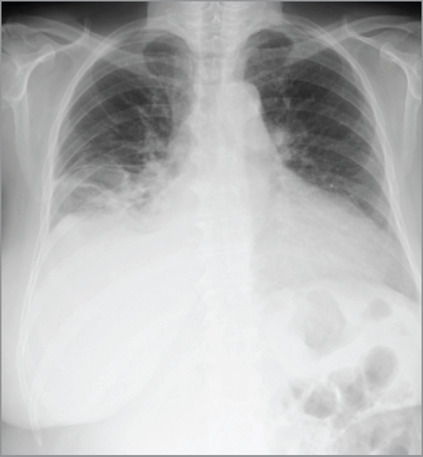

左、右心室同时形成血栓极为罕见,其临床特点及预后尚不清楚。因此,治疗方法仍存在争议。本病例强调了内窥镜取栓术作为治疗心功能受限患者巨大漂浮双室血栓的可行选择的潜力。经主动脉瓣和三尖瓣入路可以有效、完全地清除血栓,从而防止进一步的栓塞并发症。

The simultaneous formation of thrombi in the left and right ventricles is extremely rare, and this condition's clinical characteristics and prognosis remain unknown. Therefore, treatment methods are still controversial. This case highlights the potential for endoscopic thrombectomy as a viable option for the treatment of giant floating biventricular thrombi in a patient with restricted cardiac function. This approach via the aortic and tricuspid heart valves allowed for effective and complete removal of the thrombi, thereby preventing further embolic complications.